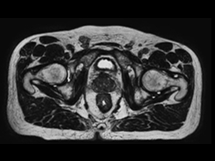

the power of the 1.5 T MR, anatomy-specific imaging sequences optimize

the visualization of the target and surrounding healthy tissue.